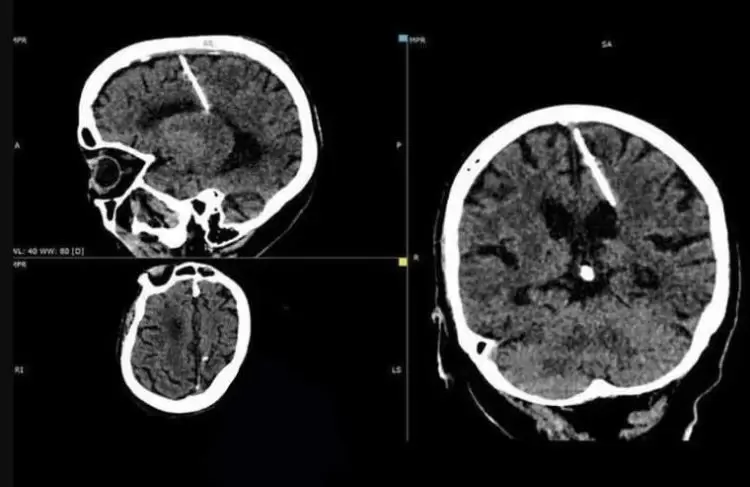

這次新聞內容的地點是俄羅斯,一位大概80多歲的老太太去醫院做檢查的時候,發現片子上接近大腦頂葉的位置竟然斜插著一根金屬針,而且看起來已經放了很長一段時間,與大腦組織和平共存到現在,這件事經過調查後曝光,也成為了前陣子俄羅斯衛生部門裡的一件奇特病例

為什麼人的大腦裡有跟針呢?這件事被爆出來後也引起了不少醫生、專家前去了解,根據老太太的年紀以及當年所處的年代,推敲出這跟針到底為什麼會出現在腦部的原因,應該是由她的父母親手插進去的,至於為什麼要這麼做呢?往回推測的結果可能是為了家裡其他成員的存活率

80多歲的老太太算算她出生的日子差不多會在1943年,當時蘇聯還處在戰爭期間,這時物資什麼的十分匱乏,因此老百姓的日子並不好過,因此老奶奶的家人為了減少一張嘴吃飯,所以做出了殘害自己小孩的決定,當時所使用的方法就是用一根針從大腦往內插下去,這跟針之後會損害大腦並且慢慢奪走小孩的生命,但意外的點就在於老奶奶生命力強大!一根針插入仍健康的活著,也許這也是讓她父母改變決定,認為既然這麼做都沒事那代表命不該絕,於是老奶奶活到了現在,而這跟針也一路待在大腦裡直到老奶奶80歲

雖然有跟針在大腦裡,但是老奶奶過往生活一切正常,也沒有頭痛或是不舒服的症狀,不過現階段醫生不認為取出是件好事,所以老奶奶接下來就是定期做檢查,而這段故事則提醒了大家那段殘酷的戰爭歲月